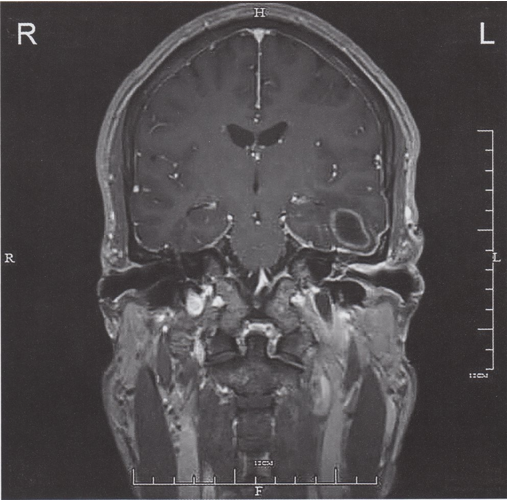

MRI head (T1 weighted; with contrast; coronal plane) of a patient with a history of left advanced otitis media In the left temporal lobe, there is an oval lesion with ring-like contrast enhancement, central low signal intensity necrosis, and perifocal edema. The walls of the left ear canal and middle ear are thickened and show contrast enhancement consistent with otitis media and otitis externa.

The appearance of the temporal lobe lesion is compatible with an abscess.